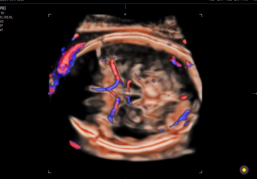

Estas tecnologías permiten la visualización de flujo microvascular en 3D y flujos sanguíneos lentos, esenciales para estudios fetales y ginecológicos. MV-Flow™ muestra la intensidad del flujo microvascular en color, mientras que LumiFlow™ ofrece una representación tridimensional del flujo sanguíneo, ayudando a comprender la anatomía vascular de manera intuitiva.